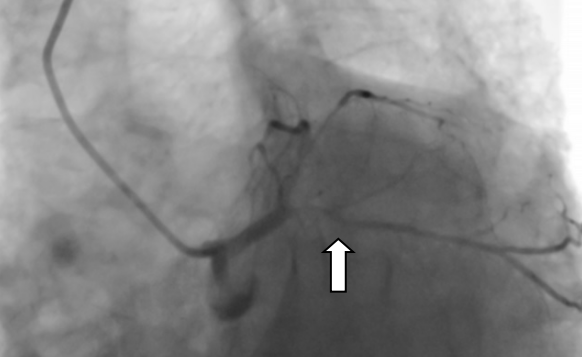

▲冠状动脉内膜旋磨术进行中。 通俗说钙化:血管里的“水垢”是什么? 提到冠心病,大家并不陌生,但冠脉钙化是什么?简单来说,就像家里用了几十年的水管,内壁会慢慢结满厚厚的水垢,血管也会因年龄增长、代谢变化,在血管壁上形成坚硬的钙化斑块——这种斑块质地坚硬,会不断变厚、缩小血管管腔,导致心脏供血不足,严重时会引发胸痛、心肌缺血,甚至危及生命,对高龄老人来说,风险更为突出。 九旬老人的难题:血管堵得只剩细缝 冯伯的案例就是典型的高危冠脉钙化情况。他因反复胸痛就医,冠脉造影检查发现,心脏三支主要供血血管均出现病变,其中最关键的供血血管——左前降支,近中段布满了厚厚的钙化斑块,血管狭窄程度高达95%,心脏供血已严重受限。更关键的是,93岁的高龄让他的血管变得壁厚、质硬、弹性差,形成了“高阻力钙化病变”,给治疗带来了极大难度。 ▲造影显示患者血管血管狭窄程度高达95%。 很多人会问,普通的心脏介入手术不能解决吗?我院心血管内科一区专家解释:“严重钙化的血管就像结满厚水垢的老旧水管,僵硬又狭窄,常规的球囊扩张术,就像用气球去吹硬邦邦的水管,根本无法将钙化斑块撑开,强行操作还可能导致血管撕裂、损伤,反而增加风险。” 对付硬钙化:“金刚钻”来帮忙 面对这种高难度的钙化病变,冠状动脉内膜旋磨术就成了针对性的治疗方式。针对冯伯的病情,医疗团队经反复评估后,决定采用这项技术为他治疗,而这项技术,也是目前应对坚硬冠脉钙化的常用微创手段之一。 冠状动脉内膜旋磨术的原理并不复杂,核心就是用“金刚钻”样的工具,精准磨掉血管内的坚硬钙化斑块。手术时,医护人员会通过微创方式,将一根顶端镶有微小钻石颗粒的橄榄型旋磨头,送入堵塞的血管内,让旋磨头以极高的速度旋转,将坚硬的钙化斑块研磨成直径小于5微米的微小微粒——这种微粒比红细胞还要小,会随着血液循环被人体自身的吞噬细胞清除,不会对身体造成额外伤害,从而打通堵塞的血管通路。 虽然原理简单,但这项手术对操作精度要求极高:既要彻底磨碎钙化斑块,打通血管通路,又要小心翼翼保护血管内壁,避免造成血管损伤。手术中,医疗团队全程精准操控旋磨头,顺利完成旋磨术后,又通过植入药物洗脱支架,进一步巩固治疗效果,防止血管再次狭窄。 术后恢复:老人终于不胸痛了 术后复查结果显示,支架贴合良好,原本严重堵塞的血管恢复了通畅,冯伯的胸痛症状缓解,心脏供血恢复正常,精神状态也日渐好转,最终顺利康复出院。 ▲支架植入术后,冠脉恢复正常供血。 结合这个案例,我们可以了解到一个重要的知识点:高龄并非复杂冠脉钙化介入治疗的绝对禁区。我院心血管内科一区主任医师陈文广表示,这类手术的成功,离不开术前精准的病情评估、术中娴熟的操作技巧以及多学科的密切配合,而这也为高龄冠脉钙化患者的治疗提供了可行的思路——经严格评估后,合适的微创技术可以有效解决这类心脏难题。 温馨提示: 正视血管钙化,及时就医 随着人口老龄化加剧,高龄、高危冠脉钙化患者越来越多,也让这类心脏问题受到更多关注。冠状动脉内膜旋磨术等微创技术的应用,不仅为这类患者提供了更多治疗选择,也让我们意识到,科学认识冠脉钙化、及时规范就医,才能更好地守护老年人群的“心”健康。 心血管内科一区简介 基本概况 我院心血管内科一区现有医护人员32名,开放床位46张,其中重症监护室(CCU)床位14张。科室配备数字减影血管造影机、血管内超声仪、血管内旋磨仪、主动脉内球囊反搏仪、心排血量监测仪等专业医疗设备,为临床诊疗工作提供硬件支持。 诊疗技术 科室在冠心病、心力衰竭、心律失常、主动脉夹层、心脏瓣膜病、心肌病、外周血管闭塞性疾病等心血管疾病的诊疗方面积累了丰富经验,针对急性心肌梗死、心源性休克、急慢性心力衰竭、主动脉夹层或动脉瘤、严重心律失常等急危重症病例,开展规范的诊断与救治工作。 临床工作中,科室常规开展心血管介入检查及治疗项目,包括冠脉支架植入术、冠脉血管内旋磨术、心脏射频消融术、主动脉腔内隔绝术、永久起搏器植入术、下腔静脉滤器植入术、肾动脉支架植入术、下肢动脉支架植入术等。 科室曾在“县域中国医院品牌专科评选”中获评第二名,先后获得“阳江市青年文明号”称号,连续多年被评为医院先进科室,团队始终秉持严谨务实的工作作风,为患者提供专业的医疗服务。 专家简介 陈文广 心血管内科主任医师,心血管内科一区主任、教授,心血管介入学科带头人、胸痛中心医疗总监。 担任广东省医师协会心脏病器械辅助治疗医师分会第三届委员会常务委员、广东省医师协会心血管内科医师分会第四届委员会委员、广东省卫生经济学会心血管疾病分会常务委员、广东省中医药学会心力衰竭专业委员会第二届常务委员、广东省基层医药学会中西医结合心血管专业委员会第二届常务委员、广东省中西医结合学会心血管介入专业委员会委员、广东省中医药学会心脏血脉专业委员会委员、广东省医师协会心脏起搏与电生理专医师分会第二届委员会基层医院心脏起搏与电生理专业组成员,阳江市医学会心脏介入分会第二届委员会副主任委员、,阳江市医学会心血管内科分会第二届委员会副主任委员、阳江市医师协会心内科医师分会第二届委员会副主任委员等。参与国家级临床科研项目1项,省级及市级临床科研项目多项;撰写著作多本,发表10多篇省级以上论文。 擅长领域:从事心血管疾病介入治疗10多年,累计有5000多例冠状动脉支架植入术(PCI)的手术经验。擅长冠心病、高血压、心衰、主动脉夹层、心脏瓣膜病、心律失常等心血管疾病的诊治,熟练掌握冠心病、左主干病变、多支血管病变、高危病变、钙化、分叉、慢性闭塞病变、临时及永久起搏器植入、主动脉覆膜支架腔内隔绝术、下腔静脉滤器植入、外周血管介入治疗等介入技术治疗。 崔 跃 心血管内科副主任医师,心血管内科一区副主任。 广东省医师协会高血压分会委员、阳江市医学会心血管分会常务委员、阳江市医学会心脏介入分会常务委员、阳江市医师分会心血管分会常务委员。参与国家级临床科研项目1项,市级临床科研项目3项;撰写著作1本,发表6多篇省级以上论文。曾多次到上级医院心血管内科进修学习,其中到中山大学第一附属医院进修心血管重症班,另先后三次到南方医院附属珠江医院进修学习心血管介入技术。 擅长领域:熟练掌握心血管介入技术,独立完成冠状动脉造影手术和冠状动脉介入手术,擅长心肌梗死、恶性心律失常、急重症心衰等的抢救。 黄 毅 心血管内科副主任医师,介入科副主任,胸痛中心秘书及协调员。 广东省胸痛中心协会委员、广东省介入学会结构性心脏病分会委员、广东省健康管理学会肺血管病专业委员会委员、阳江市医学会心血管内科分会常务委员、阳江市医学会心脏介入分会常务委员、阳江市医师协会心内科医师分会委员,阳江市医学会心脑同治分会常务委员。主持阳江市卫生健康局科技研究立项1项,主持阳江市科学技术局科技研究立项3项,参与阳江市科学技术局科技研究多项。主编《高血压及相关疾病现代诊疗》,发表国家级专业论文4篇、省级专业论文2篇。2010年毕业于广东医科大学临床医学专业,毕业后一直从事心血管内科工作,曾先后到南方医科大学珠江医院进修学习冠心病介入技术(PCI)和广东省人民医院心研所(国家班)进修结构性心脏病(包括先天性心脏病介入封堵、左心耳封堵、二尖瓣狭窄球囊扩张、肺血管病介入等)。 擅长领域:主要致力于冠心病介入、结构性心脏病介入(包括先天性心脏病介入封堵、左心耳封堵、二尖瓣狭窄球囊扩张、肺血管病介入等)、B型主动脉夹层介入、下肢动脉闭塞介入、高血压、急慢性心力衰竭、肺动脉高压的诊断与治疗。 许军国 普通内科副主任医师。 阳江市医学会心血管分会委员、阳江市医师分会心血管分会委员。1996年广东医学院临床医学毕业。曾到暨南大学第一附属医院进修重症医学科,2020年在中山大学附属第一医院进修心血管重症科CCU。 擅长领域:从事心血管疾病诊治工作25年,擅长心血管疾病重症治疗,在冠心病心肌梗死、高血压、心律失常、心力衰竭等疾病治疗上有丰富临床经验。 李昌利 心血管内科副主任医师。 阳江市医学会脑心同治分会第二届委员会常务委员、阳江市医学会心血管内科分会委员、阳江市医学会心脏介入分会委员、阳江市医师协会心内科医师分会委员。毕业于广东医学院(今广东医科大学),毕业后在阳春市人民医院工作至今。 擅长领域:擅长治疗高血压病、冠心病、心力衰竭、房颤、下肢静脉血栓等心血管疾病。 张智华 心血管内科副主任医师。 阳江市医学会脑心同治分会第二届委员会常务委员、阳江市医学会心血管内科分会委员、阳江市医学会心脏介入分会委员、阳江市医师协会心内科医师分会委员。毕业于广东医科大学临床医学专业,2016年到南方医科大学珠江医院进修学习冠心病介入技术。2021年在中山大学附属第一医院进修心血管内科。 擅长领域:擅长冠心病、高血压、心力衰竭、心律失常的诊断与治疗,熟练掌握冠状动脉介入操作及冠状动脉介入治疗技术。 滕 超 心血管内科主治医师。 阳江市医学会脑心同治分会第二届委员会常务委员、阳江市医学会心血管内科分会委员、阳江市医学会心脏介入分会委员、阳江市医师协会心内科医师分会委员。毕业于广西中医药大学,2019年到广东省人民医院进修学习冠心病介入技术。 擅长领域:擅长冠心病、高血压病、心力衰竭、下肢深静脉血栓形成等疾病的诊治。熟练掌握冠状动脉造影及冠状动脉介入治疗技术。 莫介超 心血管内科主治医师。 阳江市医学会脑心同治分会第二届委员会常务委员、阳江市医学会心血管内科分会委员、阳江市医学会心脏介入分会委员、阳江市医师协会心内科医师分会委员。毕业于广东医科大学临床医学专业,2016年到南方医科大学珠江医院进修学习心血管内科,2023年到中山医科大学附属第一医院进修心律失常介入技术。 擅长领域:擅长心律失常、冠心病、心力衰竭、高血压等疾病的诊断与治疗。 刘艺豪 心血管内科主治医师。 阳江市医学会脑心同治分会第二届委员会常务委员、阳江市医学会心血管内科分会委员、阳江市医学会心脏介入分会委员、阳江市医师协会心内科医师分会委员。毕业于广东医科大学临床医学专业,2020年在中山医科大学第一附属医院进修心血管内科。 擅长领域:从事心血管疾病诊治多年,擅长高血压病、急性心肌梗死、冠心病、心肌病、心律失常等疾病以及各种心脏急症、内科危重症的救治。 张杰亮 心血管内科主治医师。 阳江市医学会脑心同治分会第二届委员会常务委员、阳江市医学会心血管内科分会委员、阳江市医学会心脏介入分会委员、阳江市医师协会心内科医师分会委员。2015毕业于广东医科大学临床医学专业,2020年完成全国内科规范化培训。 擅长领域:擅长冠心病、高血压病、心力衰竭、急性心肌梗死、心律失常等疾病以及各种心脏急症、危重症的救治。 蓝昭海 心血管内科主治医师 2017年毕业于汕头大学临床医学专业,2021年完成全国住院医师规范化培训。 擅长领域:擅长冠心病、高血压病、心力衰竭、急性心肌梗死、心律失常等疾病以及各种心脏急症、危重症的救治。